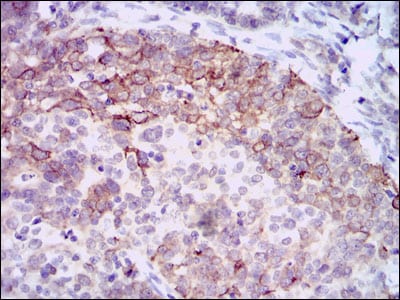

分类: 科研抗体货号: 30368别名: NOS; INOS; NOS2A; HEP-NOS应用: WB,IHC,FCM反应种属: Human,Mouse,Rat,Monkey